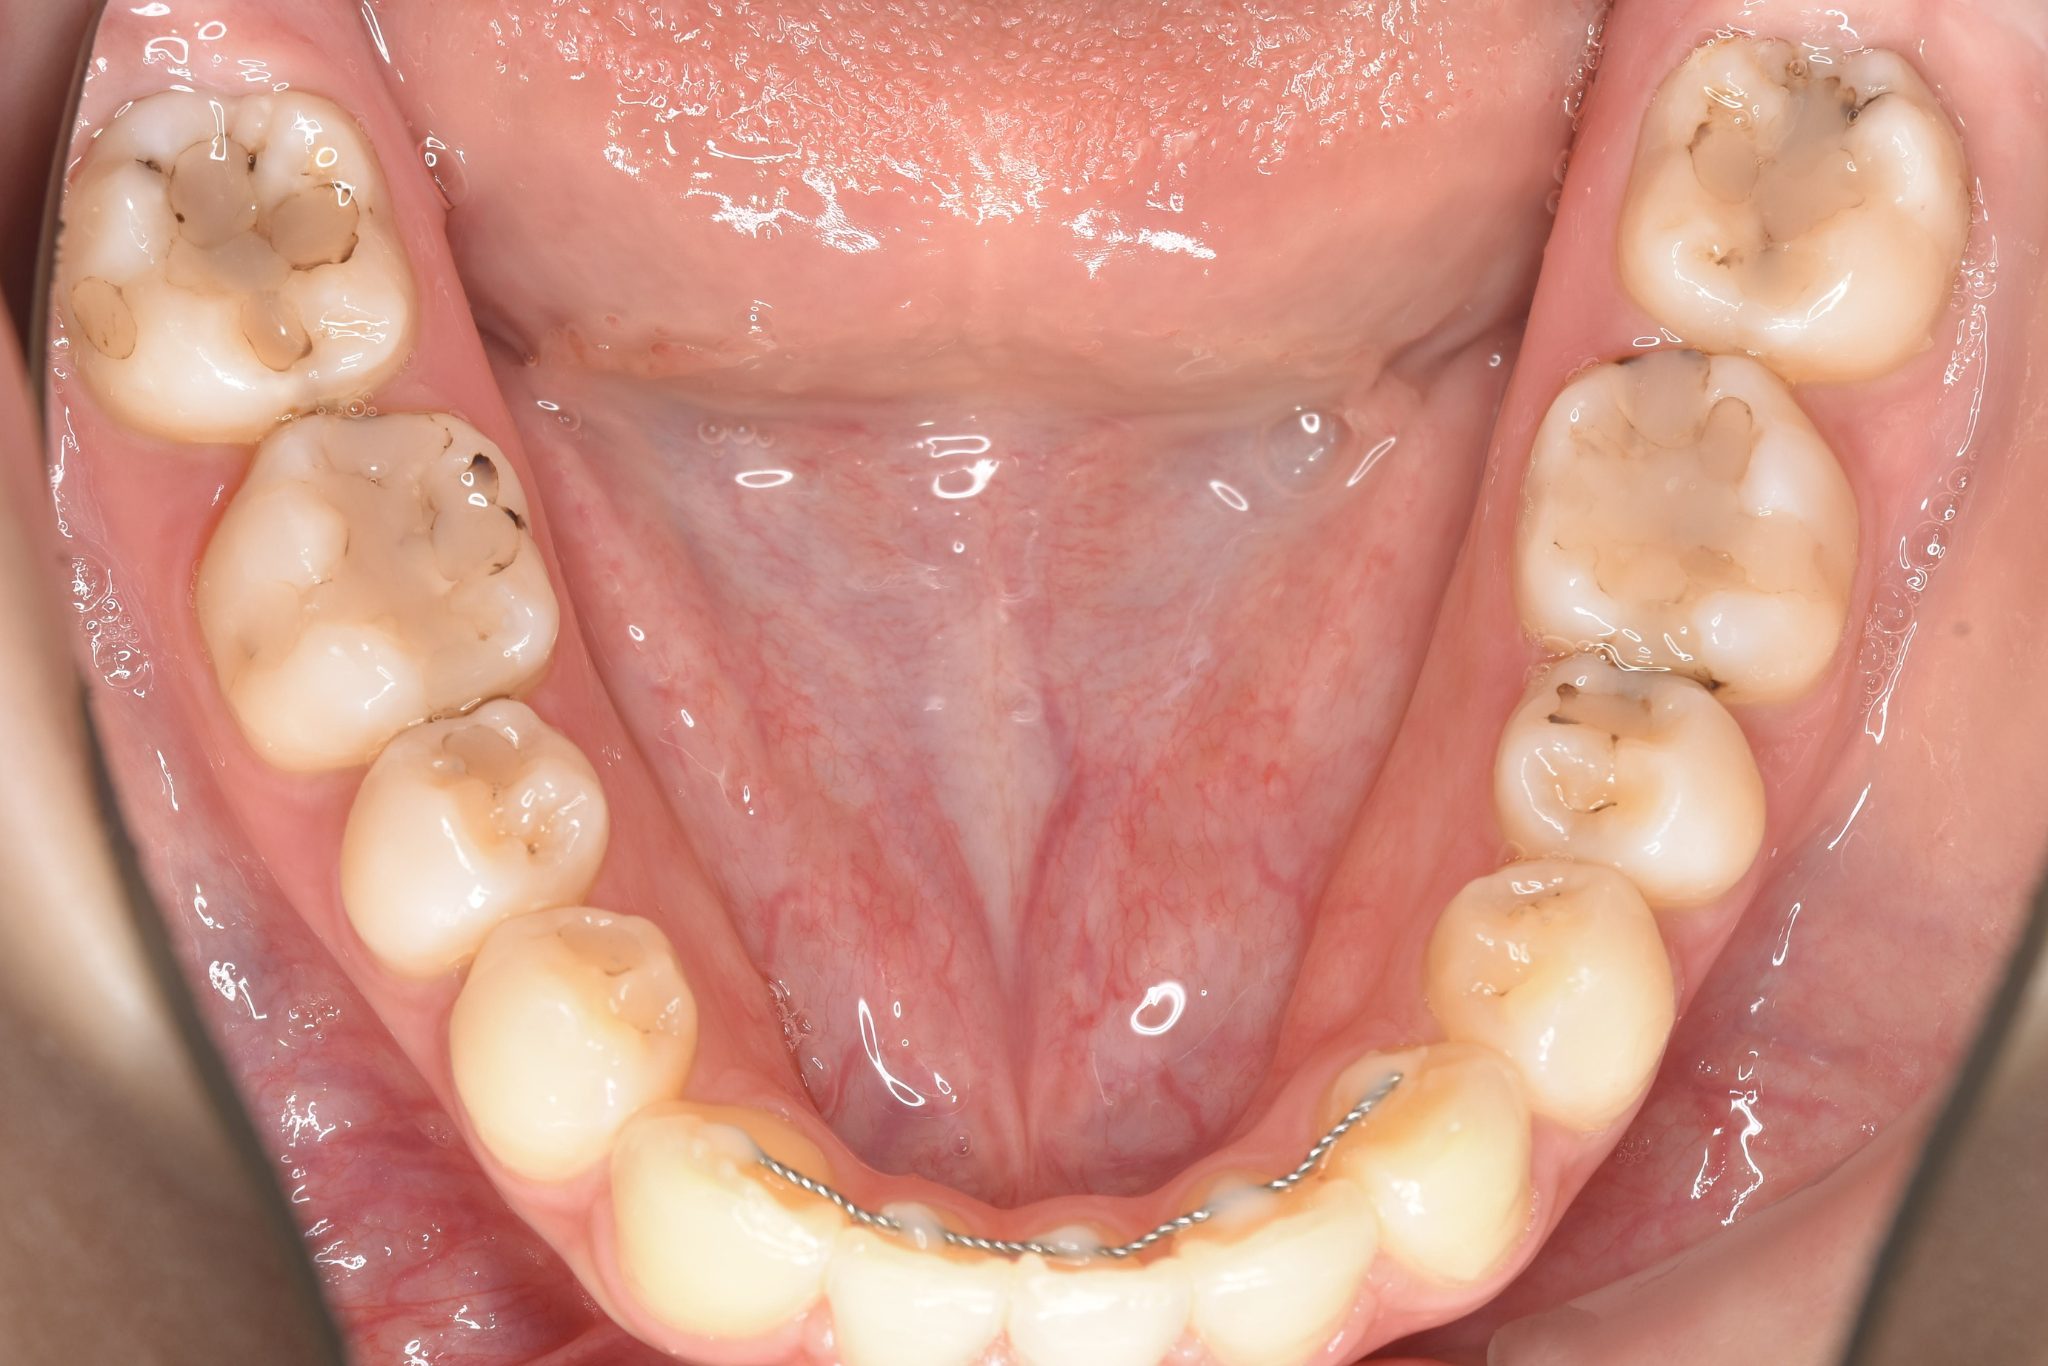

アフター

ワイヤー矯正治療|症例_009

施術内容 MSEと下顎リンガルアーチを用いて上下顎骨を拡大した。

その後マルチブラケット装置とミニインプラントを用いて非抜歯で歯牙を配列した。

下顎前歯が1本先天性欠損であったが、良好な咬合を獲得した。口元の突出感と鼻閉症状は改善された。